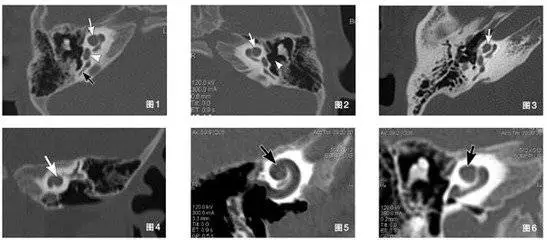

圖1-6顯示患者雙側(cè)耳蝸mondini畸形

對(duì)于術(shù)后的患者,多排螺旋CT可直觀觀察植入電極的形態(tài)及位置,準(zhǔn)確評(píng)估電極在耳蝸內(nèi)植入的數(shù)目,有重要的臨床價(jià)值。

多排螺旋CT主要觀察內(nèi)耳結(jié)構(gòu)(骨迷路結(jié)構(gòu))。耳蝸畸形中,除Michel畸形、耳蝸未發(fā)育為手術(shù)的絕對(duì)禁忌癥,其他類(lèi)型內(nèi)耳畸形均非人工耳蝸植入的禁忌癥。不同內(nèi)耳畸形術(shù)后可能出現(xiàn)不同的并發(fā)癥,多層螺旋CT及其后處理技術(shù),能從不同角度、由二維到三維立體顯示內(nèi)耳結(jié)構(gòu)的大體形態(tài),對(duì)不同畸形做出細(xì)致的分類(lèi),能幫助臨床醫(yī)生更好地預(yù)測(cè)手術(shù)中可能遇到的問(wèn)題,合理地選手術(shù)方式和判斷預(yù)后,有很高的應(yīng)用價(jià)值。